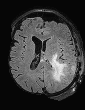

In recent years, data-driven machine learning (ML) methods have revolutionized the computer vision community by providing novel efficient solutions to many unsolved (medical) image analysis problems. However, due to the increasing privacy concerns and data fragmentation on many different sites, existing medical data are not fully utilized, thus limiting the potential of ML. Federated learning (FL) enables multiple parties to collaboratively train a ML model without exchanging local data. However, data heterogeneity (non-IID) among the distributed clients is yet a challenge. To this end, we propose a novel federated method, denoted Federated Disentanglement (FedDis), to disentangle the parameter space into shape and appearance, and only share the shape parameter with the clients. FedDis is based on the assumption that the anatomical structure in brain MRI images is similar across multiple institutions, and sharing the shape knowledge would be beneficial in anomaly detection. In this paper, we leverage healthy brain scans of 623 subjects from multiple sites with real data (OASIS, ADNI) in a privacy-preserving fashion to learn a model of normal anatomy, that allows to segment abnormal structures. We demonstrate a superior performance of FedDis on real pathological databases containing 109 subjects; two publicly available MS Lesions (MSLUB, MSISBI), and an in-house database with MS and Glioblastoma (MSI and GBI). FedDis achieved an average dice performance of 0.38, outperforming the state-of-the-art (SOTA) auto-encoder by 42% and the SOTA federated method by 11%. Further, we illustrate that FedDis learns a shape embedding that is orthogonal to the appearance and consistent under different intensity augmentations.